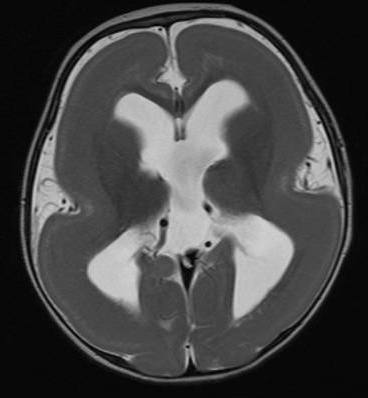

Computed Tomography (CT) is an imaging modality that utilizes X-ray technology to generate detailed cross-sectional images of the body.

CT scans provide a significantly higher radiation dose, which poses potential risks, particularly for paediatric patients who may require multiple scans over time. Despite this concern, the speed and efficiency of CT make it an invaluable tool for expediting critical neurosurgical decisions, especially in emergency trauma situations where rapid diagnosis is essential.

CT scans excel in visualizing complex conditions, offering superior insights into injuries such as fractures, and diagnosing craniosynostosis—a congenital disorder where the skull bones fuse prematurely. Additionally, they are adept at detecting intracranial calcifications, which are deposits of calcium or other minerals within the brain, and diagnosing intracranial hemorrhages, which indicate bleeding within the cranial cavity.